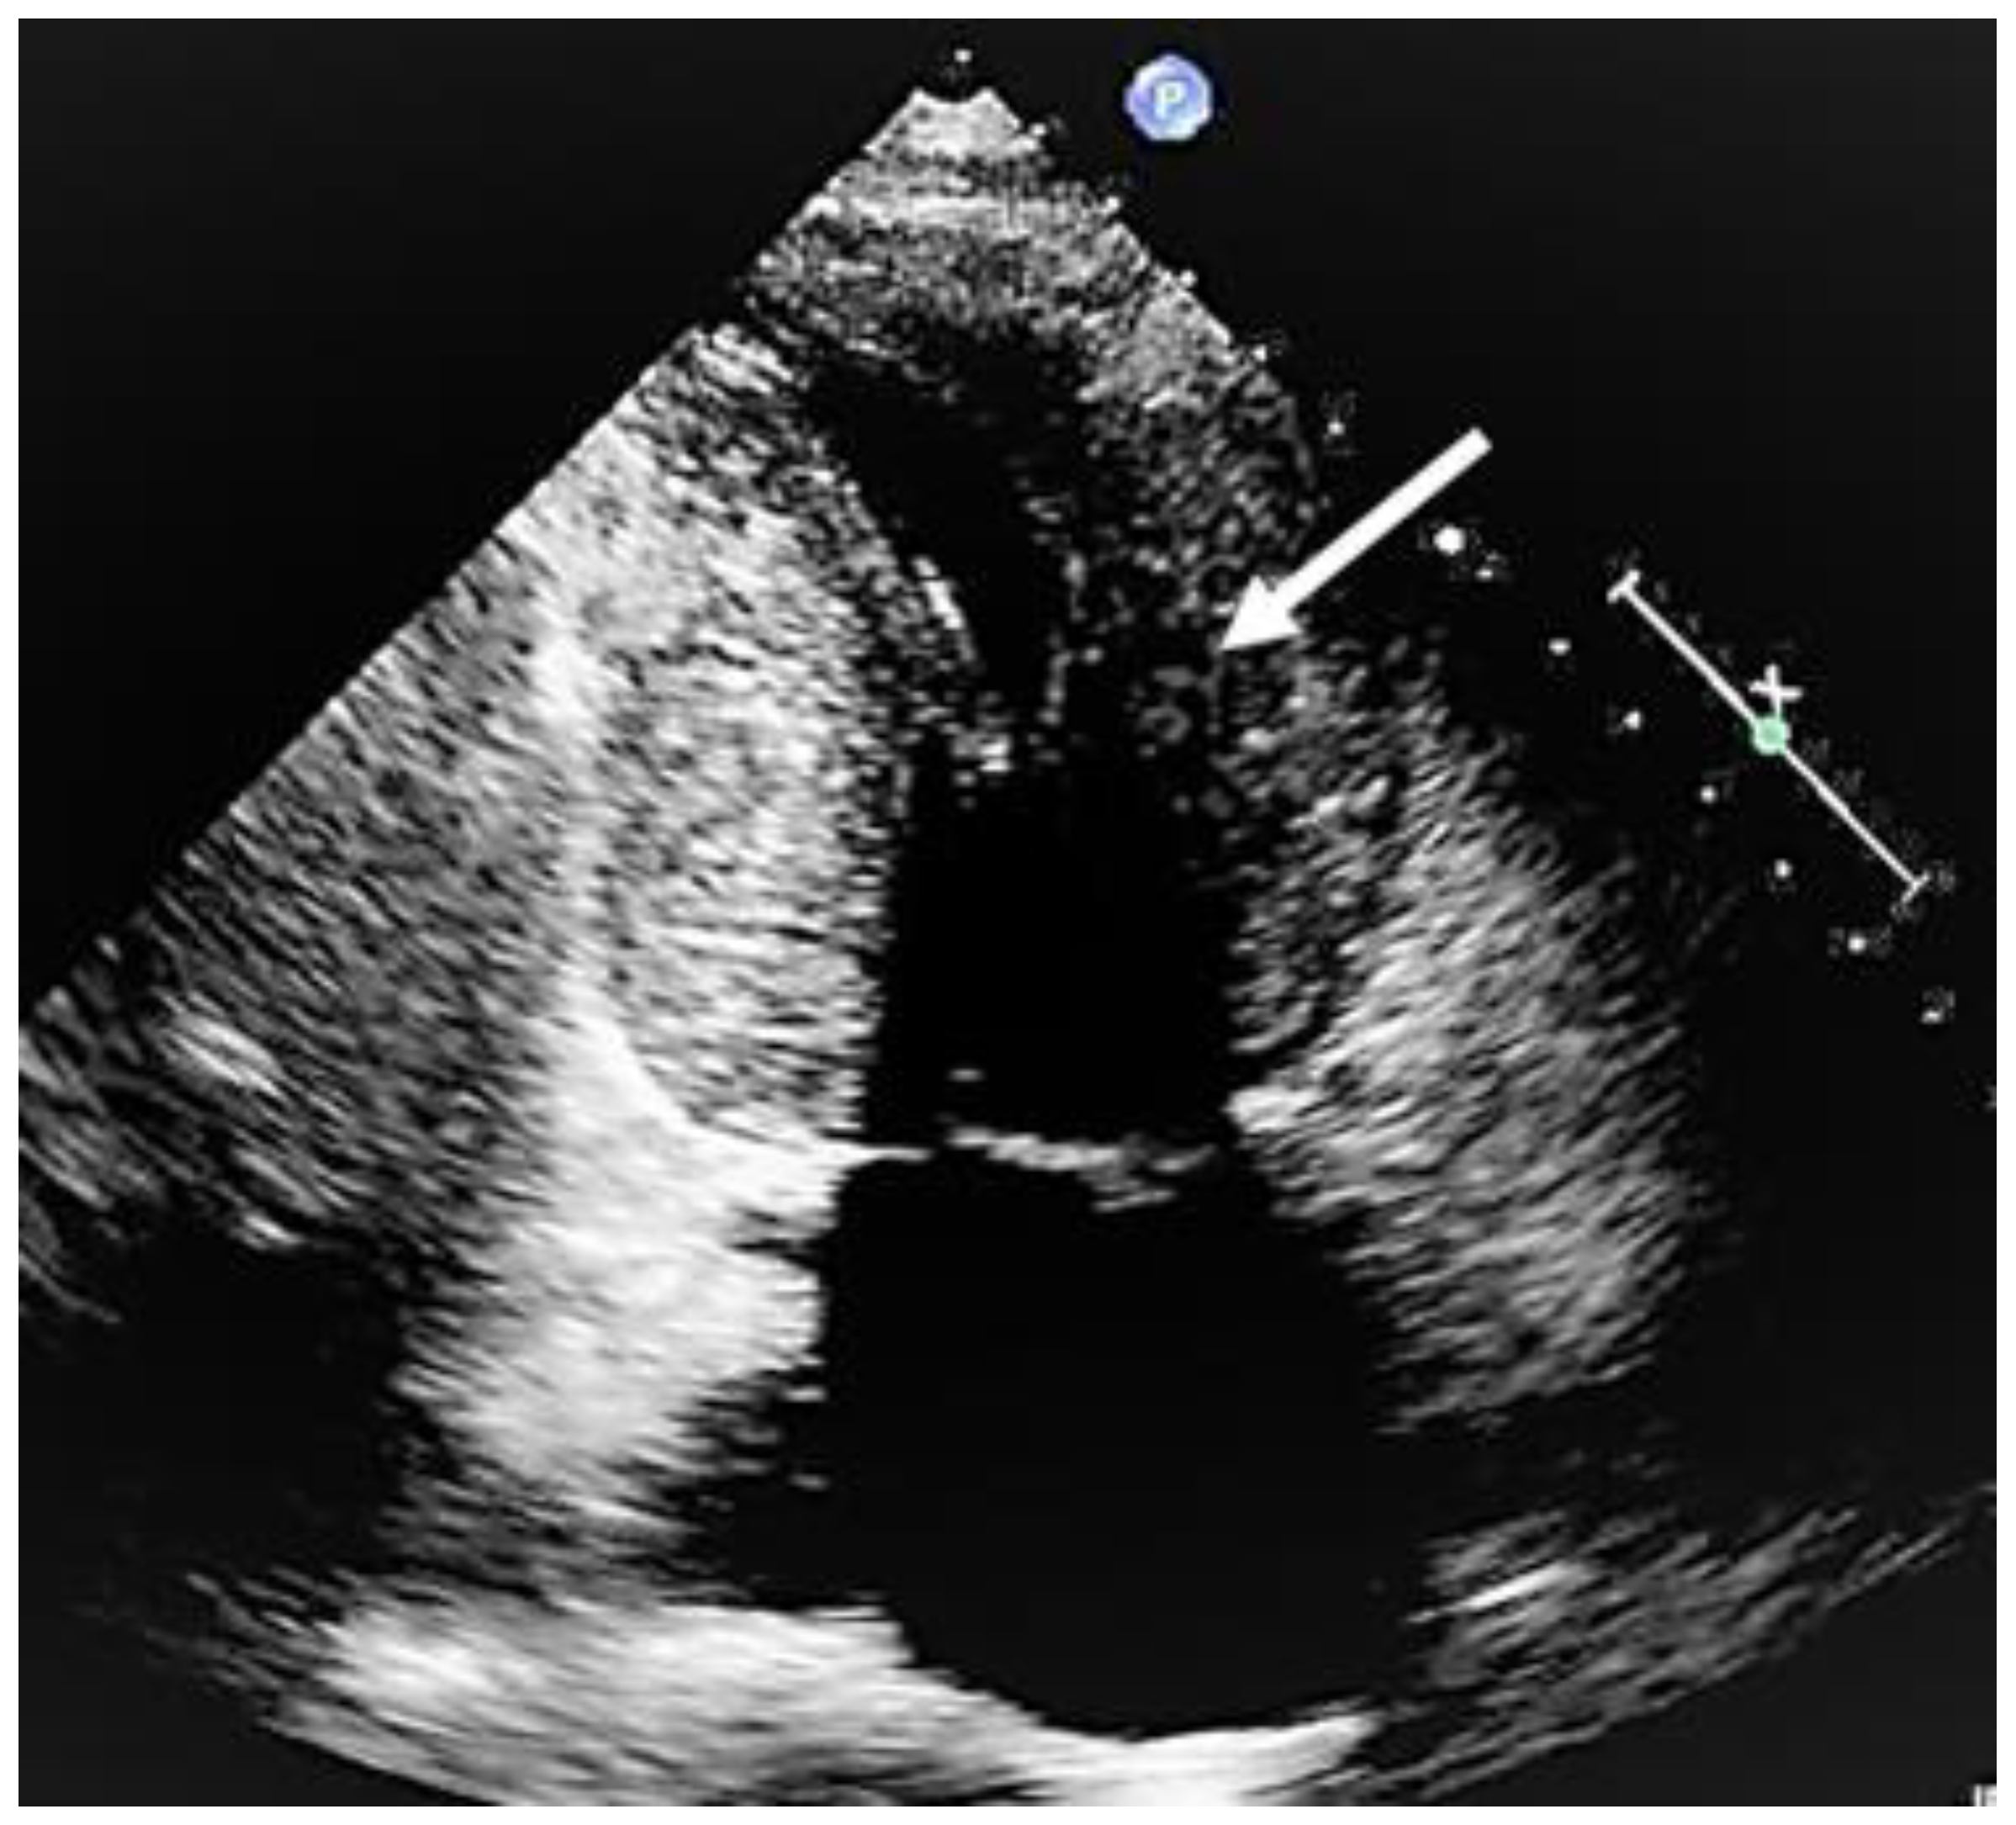

When evaluating the presence and severity of obstruction in HCM, a systematic assessment of all the components of the mitral valve apparatus via 2D echocardiography is required. This technique allows a visualization of the presence and distribution of LV hypertrophy, the presence of SAM, elongation of mitral valve leaflets, displacement of papillary muscles, laxity of tendon cords and LVOT diameter reduction (Figure 2). In addition, 2D echocardiography allows a diagnosis of MCO via the observation of a typical hourglass appearance of the LV due to systolic septal contact with the anterolateral wall, which induces sphincter-like cavity obliteration, creating two distinct (basal and apical) LV chambers (Figure 5). In addition, 2D echocardiography allows a visualization of the presence of an apical aneurysm and any thrombotic formation. In this setting, contrast echo may also be helpful for the correct diagnosis.

Figure 5.

Mid-cavity obstruction; typical hourglass appearance of left ventricle (arrow).